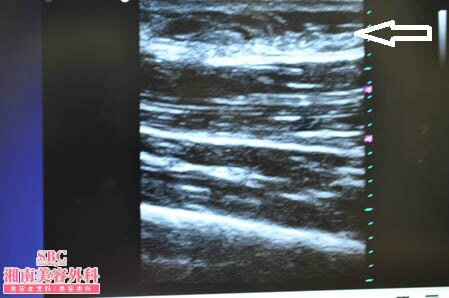

No.177936【脂肪吸引】圧倒的吸引量で圧倒的満足度!あの有名な根こそぎ竹田先生の劇的ビフォーアフター!〜他院の再手術!左太もも3Dタッチビュー〜

左太もも3Dタッチビュー

→

まずは3Dタッチビュー(超音波)の出番ですね。

患者様にはこの画像を手術終了後に

見ていただきました。

そしてもちろんご納得いただきました。

皮下脂肪の取り残しがないことが

患者様に画像で見ていただける3Dタッチビュー。

大人気です!!